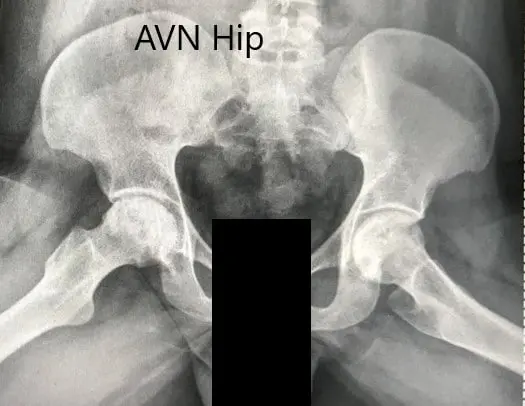

An X-ray was obtained which suggesting bilateral sclerosis of the head of femur and acetabulum changes. There were degenerative changes. An MRI of both hips was obtained.

Preoperative X-ray of the pelvis with both hips in the frog-legged lateral view showing AVN of both hips.